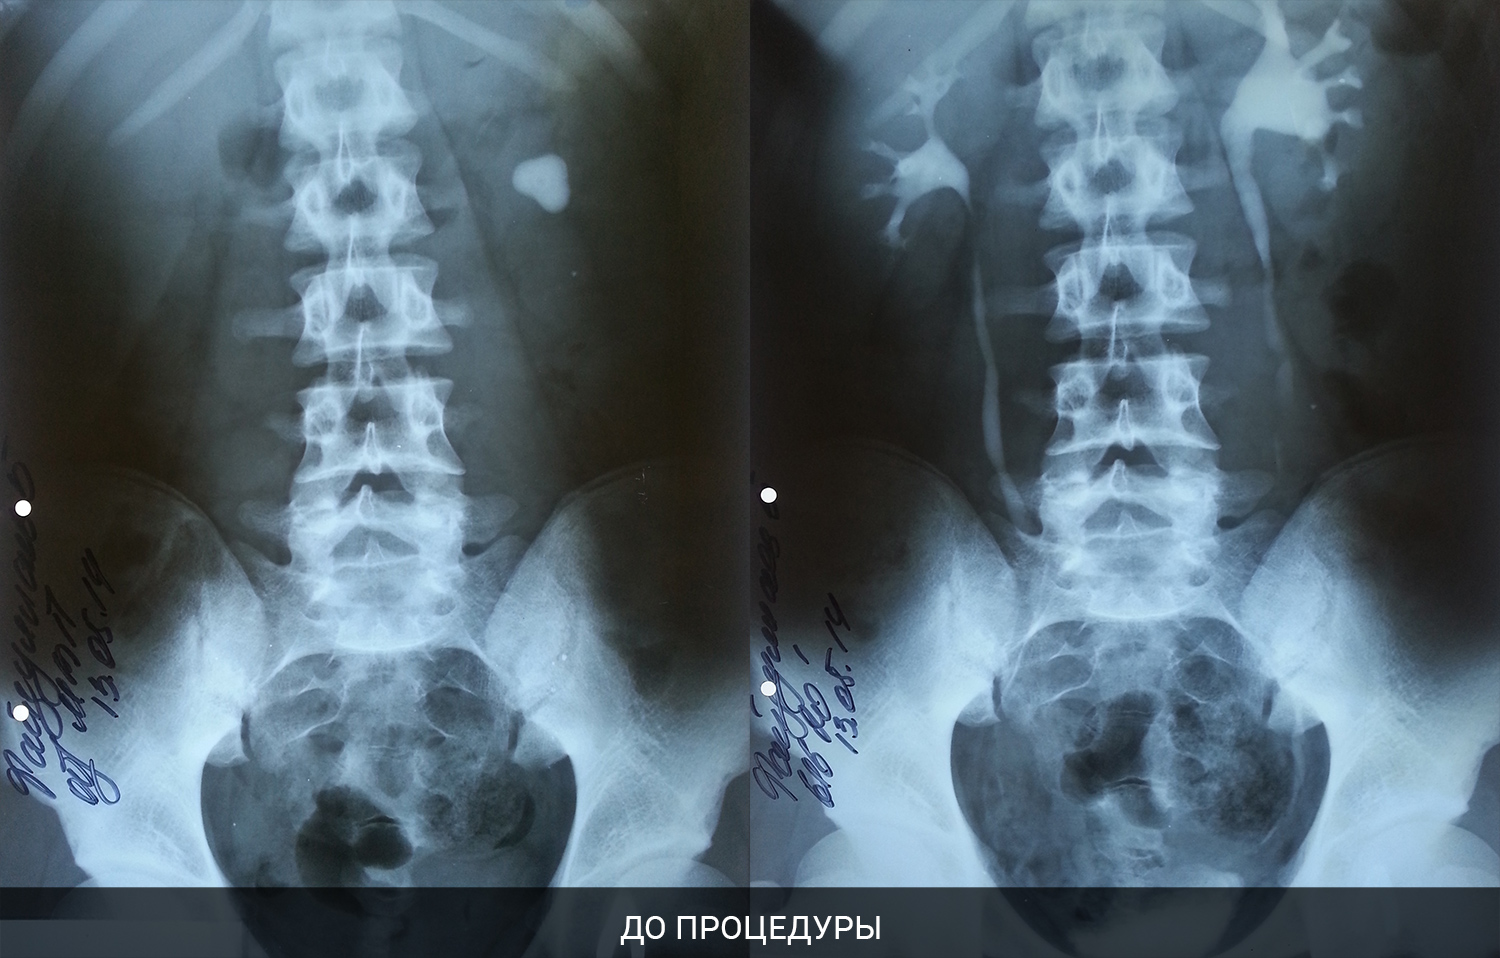

Раздел: Снимки-откровения